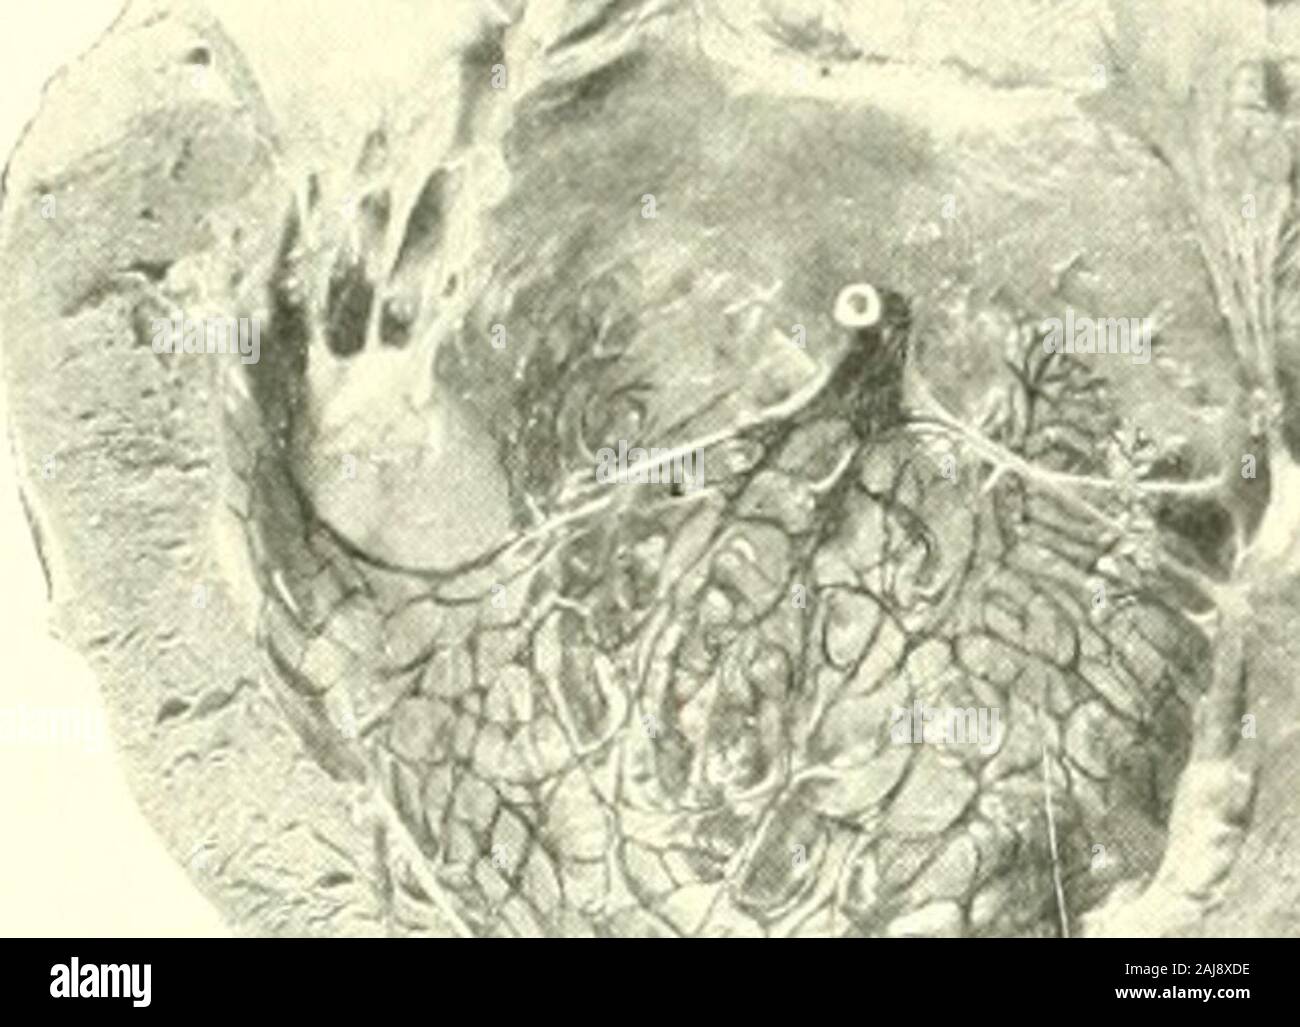

9. Extramembranous pregnancy with fetus. Note the size of fetus and the... | Download Scientific Diagram